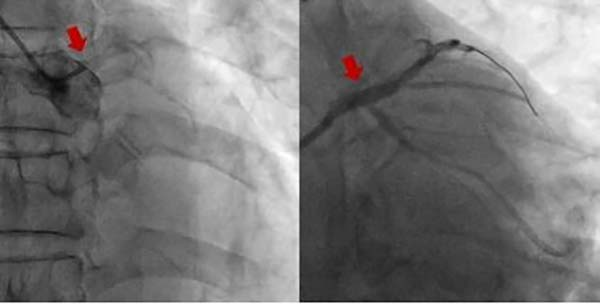

冠脉造影结果显示,患者左主干自开口完全闭塞,右冠脉重度狭窄,病情十分凶险。一方面患者生命体征不稳定,梗死面积大,心原性休克征象明显;另一方面,患者病变复杂,手术风险高、难度大。抢救的关键在于尽快开通闭塞血管,在包恩泽主任医师带领下,梁超、刘文博医师及王克技师快速完成IABP组装,顺利经股动脉置入IABP装置。随着IABP开始工作,患者血压终于能维持在100/60mmHg左右,为后续手术创造了稳定条件。

该患者左主干自开口闭塞,且合并严重钙化,导致指引导管到位、导丝通过病变、介入器械的输送均面临巨大挑战。包恩泽主任医师凭借丰富的经验与规范的操作流程,与团队默契配合、沉着应对,逐一攻克技术难题。最终,从患者入院到成功开通闭塞血管仅用时74 分钟,并顺利完成冠脉支架置入手术。